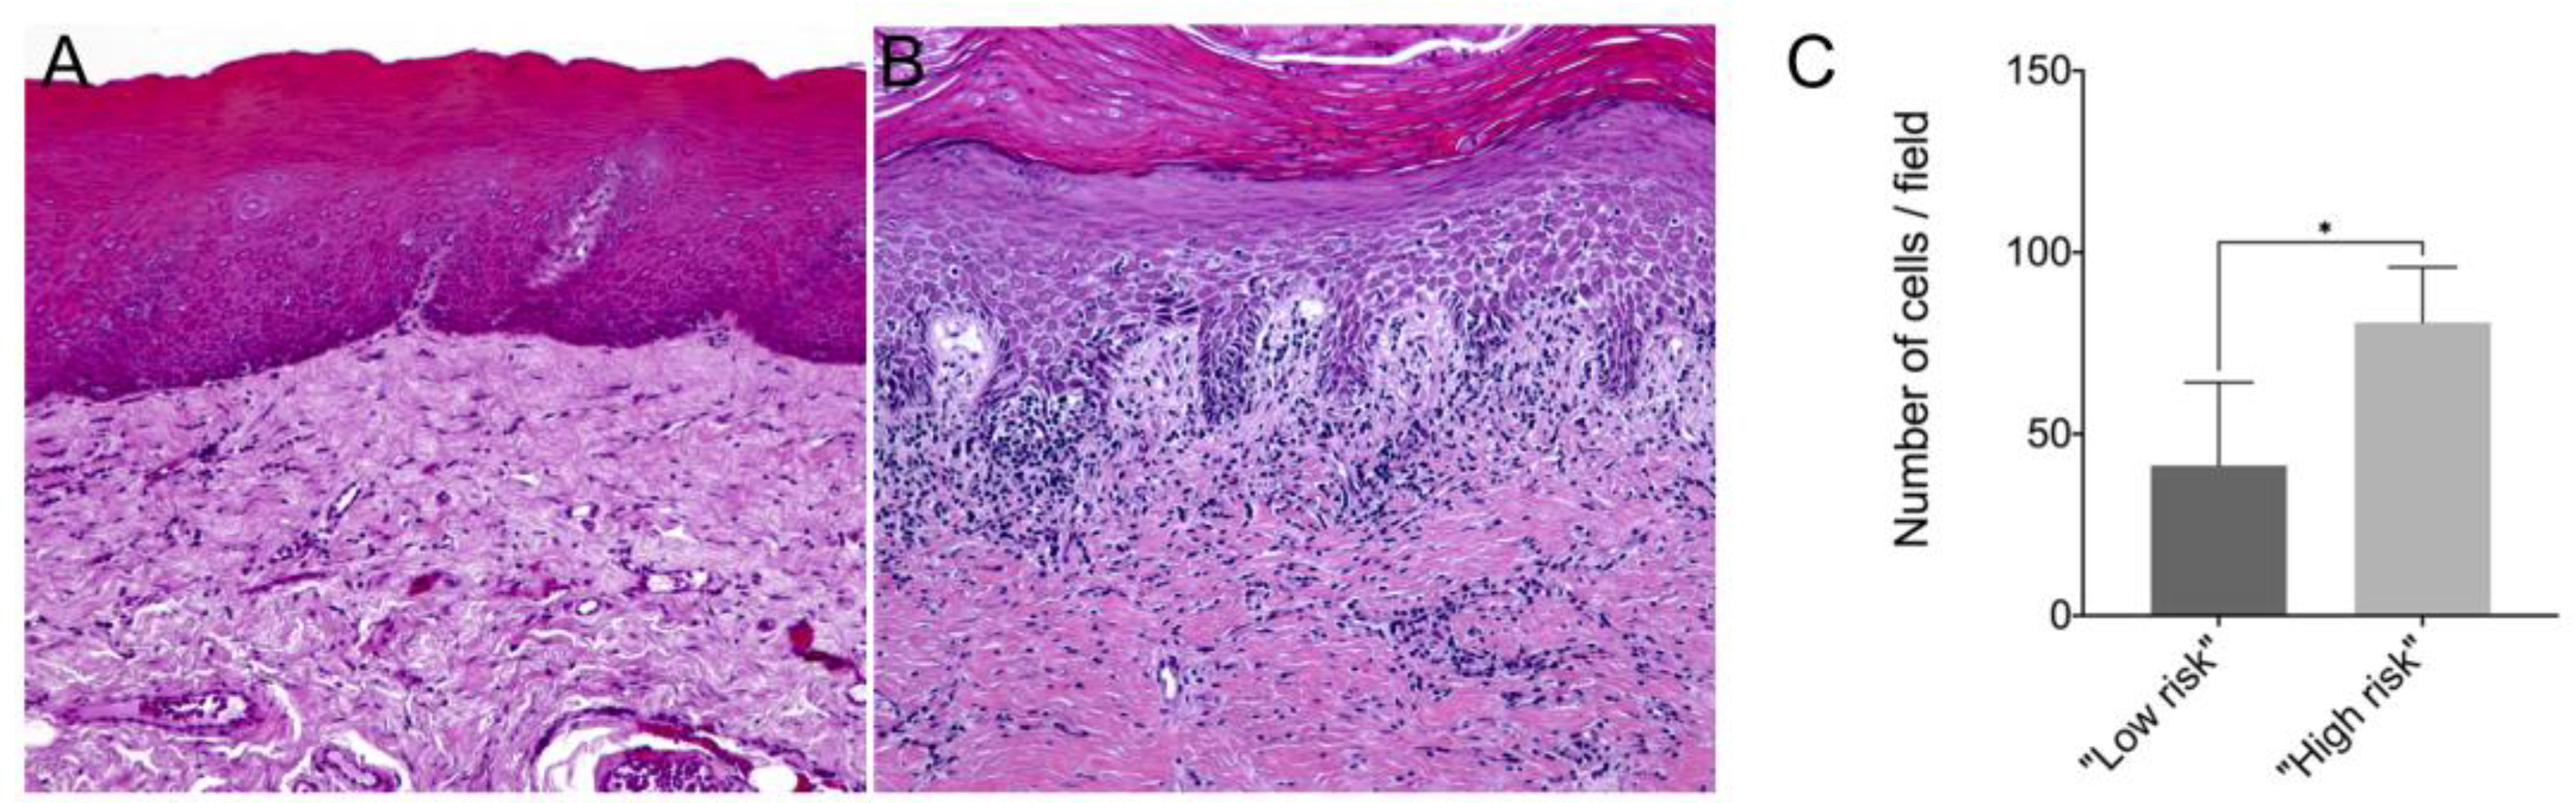

In this study, we showed that the frequency of subepithelial inflammatory cells was significantly higher in samples classified as “high risk” compared to “low risk” samples (95% CI: 0.000 to 93.20; p = 0.006), predominantly presenting a chronic lymphoplasmacytic inflammatory infiltrate (Figure 1). Furthermore, it has been demonstrated through immunofluorescence that dysplastic oral lesions exhibit hypoacetylation of H3K9 and low levels of γH2AX compared to the control group (IFH). Considering the H3K9ac intensity of labeling, there was a statistically significant reduction in H3K9ac levels between the “low-risk” (95% CI: 2854.89 to 6274.81; p < 0.001) and “high-risk” groups (95% CI: 467.65 to 3993.28; p = 0.01) compared to the control group as well as a significant reduction in H3K9ac levels between the low-risk and the high-risk group (95% CI: −3549.90 to −1118.87; p < 0.001). On the other hand, the percentage of H3K9ac positive cells in the intraepithelial area was lower in the “low-risk” group compared to the control group (95% CI: −30.61 to −4.45; p = 0.006). In addition, H2AX phosphorylation levels decreased in “high-risk” lesions when compared to “low-risk” lesions (95% CI: −0.76 to −0.06; p = 0.015) and control (95% CI: −1.50 to −1.97; p = 0.009). Figure 2 shows the representative images of H3K9ac and γH2AX immunofluorescence and graphics of quantitative analysis.

Figure 1.

Representative image of hematoxylin–eosin (HE) staining from a (A) “low-risk” lesion biopsy and a (B) “high-risk” lesion biopsy; (C) Number of inflammatory cells per field in samples from “low-risk” and “high-risk” lesions. The mean number of immune cells counted per field in paraffin-embedded tissue samples of “low risk” and “high risk” lesions. * p < 0.05.